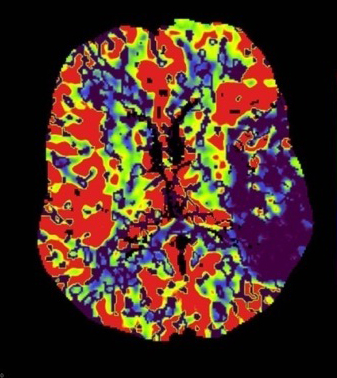

Perfuzia CT permite diferenţierea ariilor de infarctizare reală (nucleul ischemic) de ariile ischemice care sunt supuse riscului de infarctizare în lipsa terapiei trombolitice (zona de penumbră).

- în identificarea nucleului infarctului – regiuni cu CBV (volum sanguin cerebral) extrem de scăzut;

- în identificarea pacienților care prezintă zone de “țesut cu risc de infarctizare” în absența recanalizării, care pot fi recuperate cu tratament trombolitic (la debutul unui AVC acut, prezenţa unei zone de penumbră ischemică operațională reprezintă o indicaţie că terapia trombolitică poate fi benefică);